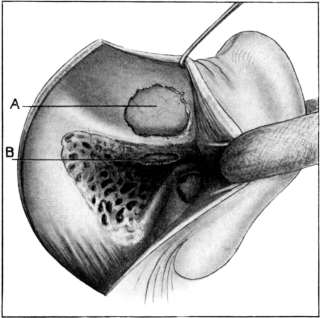

| 241. | Operation upon the Labyrinth | 424 |

| 242. | Extirpation of the Labyrinth | 425 |